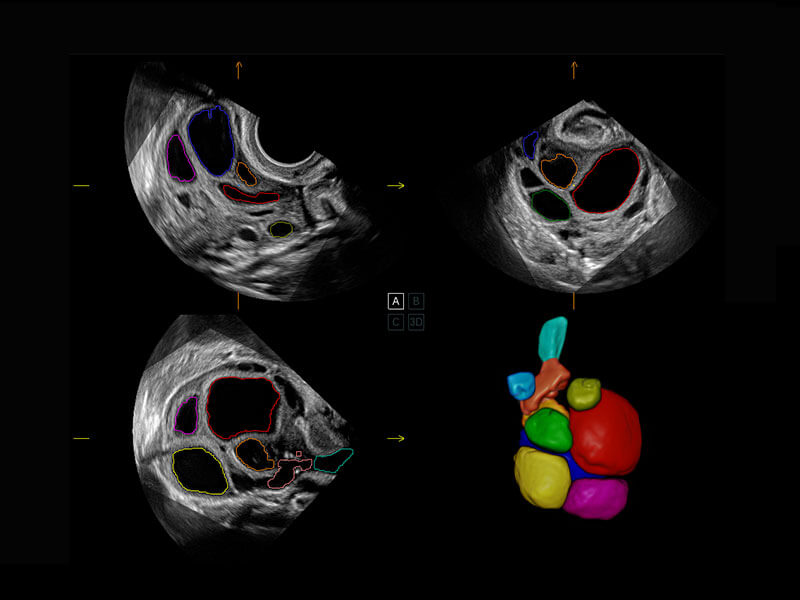

P60搭载一系列胎儿心脏成像技术,实现精细的胎儿心脏评估。

四腔切面

四腔心血流

右室双出口

胎心容积成像